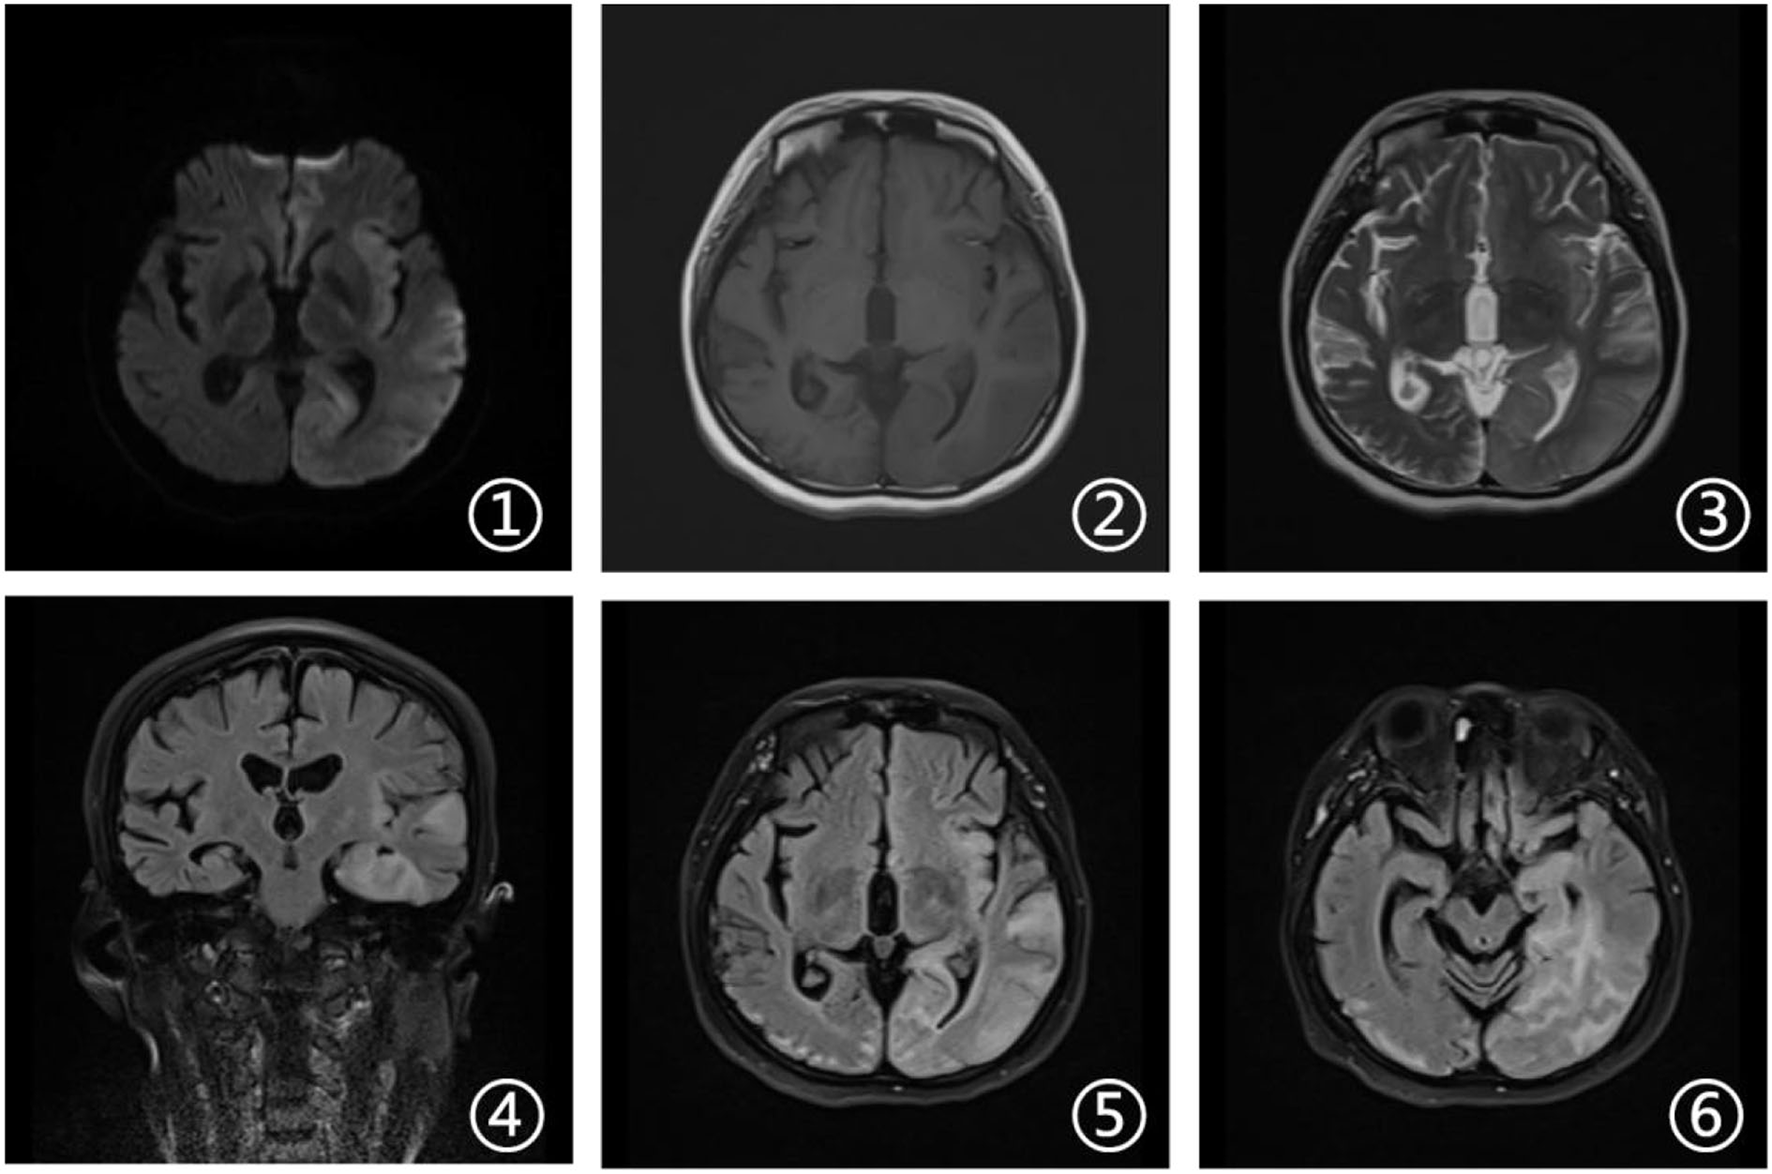

Laboratory tests and cerebrospinal fluid evaluation were normal, including the screening for autoimmune encephalitis and paraneoplastic syndromes-related antibodies. On ultrasound examination, there was no visceromegaly or evident masses. The optical coherence tomography fundus images were normal. The reduced motor nerve conduction velocity, compound muscle action potential amplitude of median nerves, and the sensory conduction velocity of peroneal and sural nerves suggested the presence of a demyelinating peripheral neuropathy. The interictal electroencephalogram (EEG) showed severe generalized slowing waves (Figure 1). Brain MRI exhibited a right occipital cortical ribbon sign on T2-weighted and fluid-attenuated inversion recovery (FLAIR) sequences, with global brain atrophy and ventricular enlargement. Diffusion-weighted imaging (DWI) and susceptibility-weighted imaging (SWI) sequences revealed no other abnormalities (Figure 2).

Figure 2

Brain magnetic resonance imaging (MRI). Axial diffusion-weighted imaging (DWI), T1-weighted, and susceptibility-weighted imaging (SWI) sequences (1, 2, and 6) revealed no other abnormalities. Axial T2-weighted and fluid attenuated inversion recovery (FLAIR) sequences (3 and 5) showed a right occipital cortical hyperintense signal. Sagittal T2-weighted scan (4) showed global brain atrophy and ventricular enlargement with occipital cortical hyperintense signal.